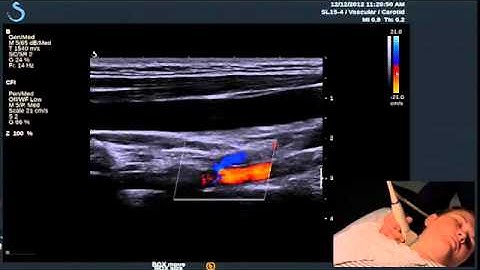

iMEP Tips & Tricks 5: Distinguishing veins from arteries when using ultrasound